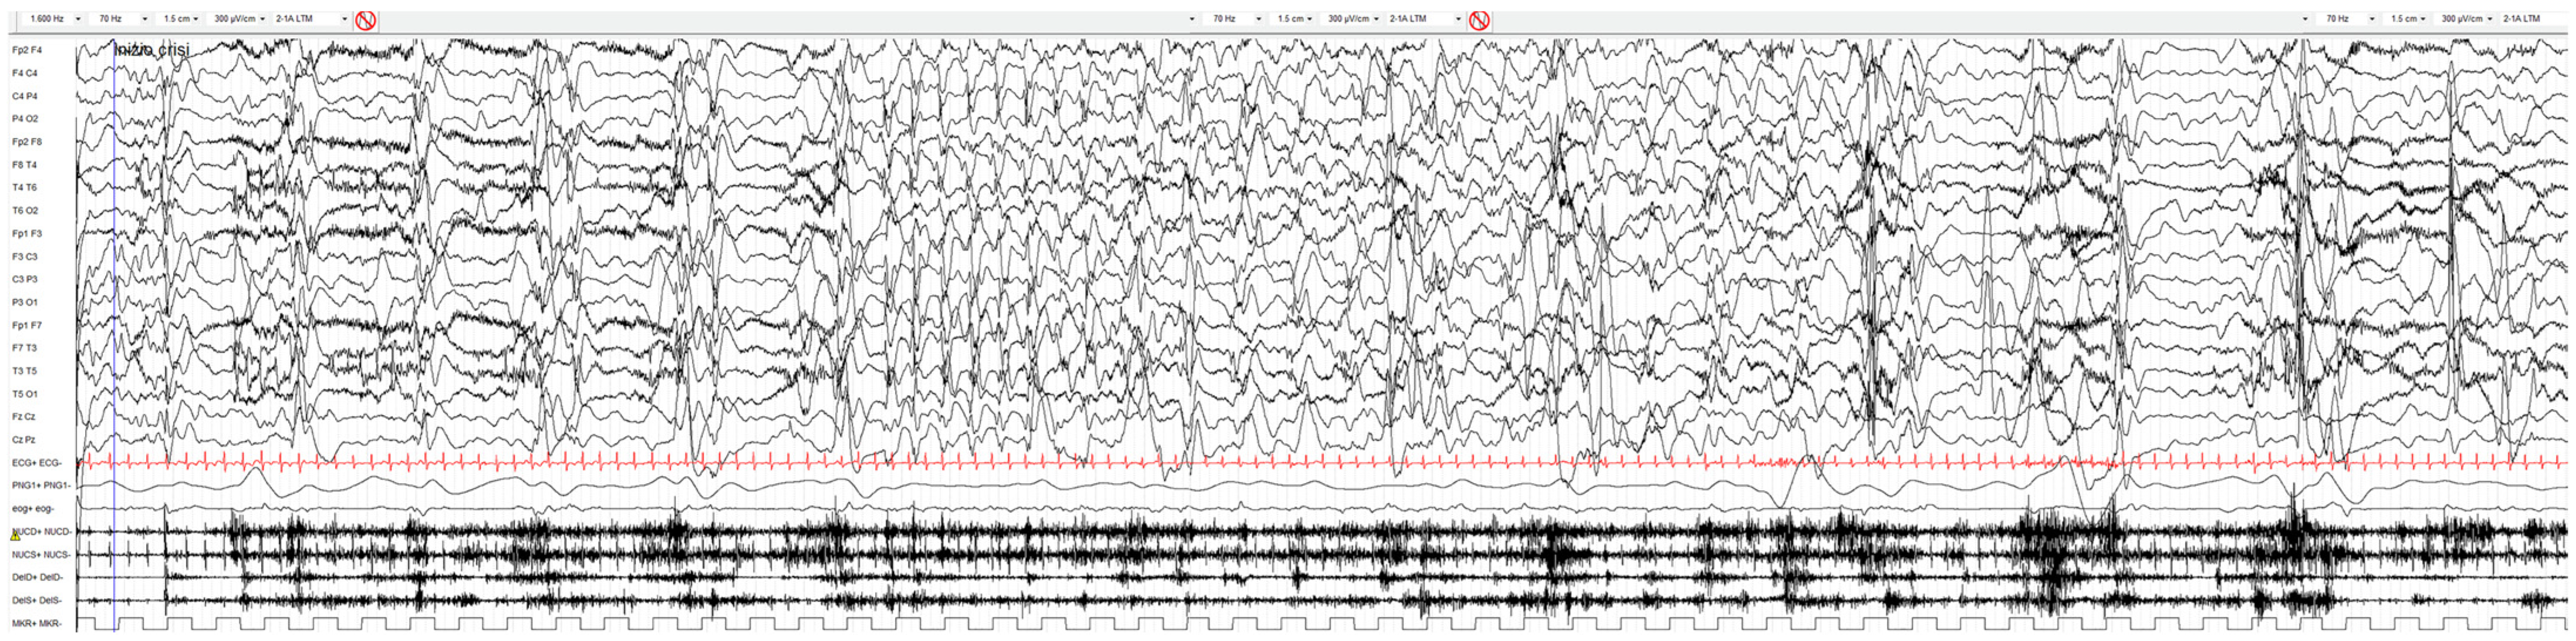

2. Case Report

- Darra, F.; Monchelato, M.; Loos, M.; Juanes, M.; Bernardina, B.D.; Valenzuela, G.R.; Gallo, A.; Caraballo, R. CDKL5-associated developmental and epileptic encephalopathy: A long-term, longitudinal electroclinical study of 22 cases. Epilepsy Res. 2023, 90, 107098. [Google Scholar] [CrossRef]